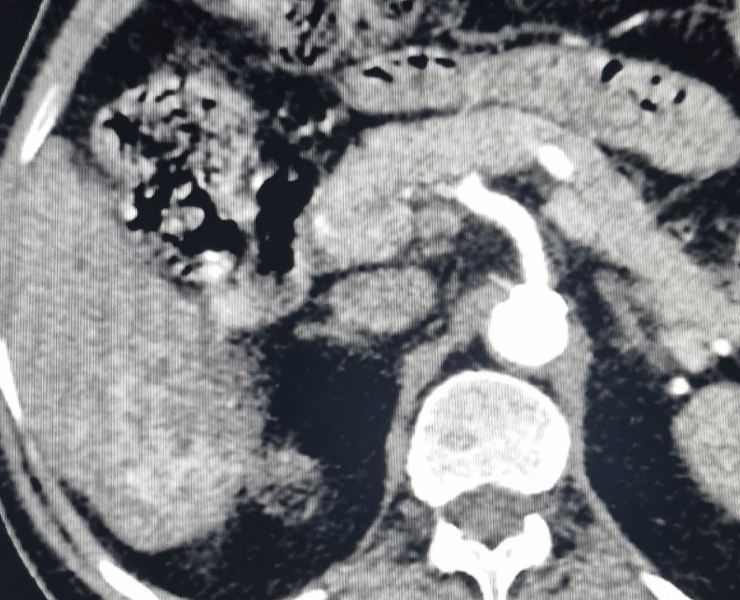

- Chemoembolization (TACE): delivers chemotherapy directly into the tumour’s blood supply, followed by embolic particles to block the vessels and cut off nutrition to the cancer.

Post treatment (TACE) procedure

Chemoembolization of liver cancer before